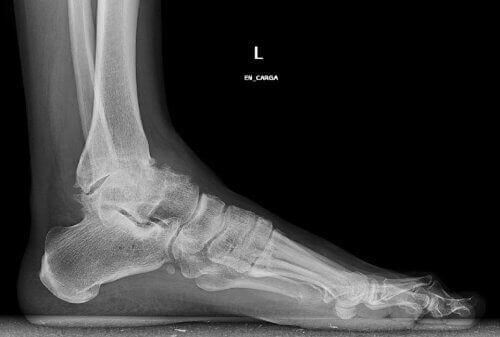

Den här typen av artros beror på varaktigt slit på brosket i fotleden. Det är vanligt att den blir stel och utvecklar deformiteter med åldern.

Klassiska osteofyter kan också uppkomma, vilket gör det till en väldigt smärtsam och begränsande åkomma.

- Traumatologer säger också att det finns ett specialfall av åkomman: deformiteten av själva fotleden. Ibland löper man större risk för att råka ut för osteoartrit med tiden bara genom att ha platta fötter.